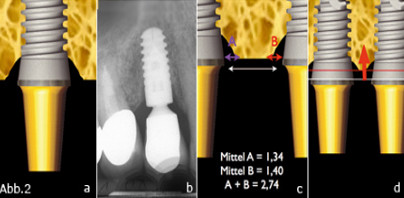

Eine Vielzahl von Implantatsystemen basiert auf außen bündigen Implantat-Abutment-Verbindungen. Externe als auch interne Verbindungen kommen hier zur Anwendung und versuchen dem Hart- und Weichgewebsinterface eine möglichst glatte und ebene Angriffsfläche zu bieten. Langzeitstudien zu Folge etabliert sich das periimplantäre Knochenniveau immer auf dem Niveau apikal dieser bündigen Verbindung zwischen Implantat und Abutment (Bullon 1999). Auch in Fällen, bei denen das Implantat bis zu seiner chirurgischen Freilegung mitsamt seiner Abdeckschraube tief im Knochen einheilt, ringsum von Knochen bedeckt ist und nur mittels Ostektomie von seiner Abdeckschraube befreit und mit einem Gingivaformer versehen werden kann, setzt bald nach der Freilegungsoperation – spätestens jedoch in der frühen Belastungsphase – ein Knochen-Remodellationsprozess ein, der die Ausprägung eines periimplantären Knochentrichters in Form eines schüsselförmigen Defekts zur Folge hat (Abb.2a und b). Dies wurde als physiologisch und unvermeidbar angesehen und als „Knochenabbau bis zur ersten Windung“ bezeichnet. Dies gipfelt sogar darin, dass die bis heute gültigen, wissenschaftlich anerkannten Kriterien für eine erfolgreiche Implantatbehandlung den Knochenverlust erst ab dem ersten Jahr nach Belastung messen (Zarb und Albrektsson 1998). Hierbei wird als völlig normal der Verlust von bis zu 2 mm an krestalem Knochen im ersten Jahr nach Belastung und 0,2 mm pro Jahr angesehen.

Abb.2 a: Trichterförmiger Knocheneinbruch um ein Implantat nach der Freilegungsoperation. b: Trichterförmiger Knocheneinbruch bis zur ersten Implantatwindung. c: Interimplantärer Abstand größer als 3mm. Die Knochenspitze kann die papillären Strukturen erhalten. d: Interimplantärer Abstand kleiner als 3mm. Das krestale Knochenniveau sinkt ab. Die Papille zwischen den beiden Implantaten verliert an Höhe.

Beide Annahmen wären mögliche Erklärungen für ein Zurückweichen, das heißt eine Resorption des Knochens, vom Mikrospalt weg unter Zwischenschaltung von Bindegewebe. Die Arbeitsgruppe um Hermann (1997, 2000 und 2001) konnte anhand einer Reihe von radiologischen und histologischen Untersuchungen demonstrieren, dass sich bei jeder möglichen Konfiguration eines zweiteiligen (ITI)-Implantats, das eine Verbindung zur Mundhöhle aufweist, eine biologische Vertikaldistanz von 2 mm zwischen Mikrospalt und erstem Implantat-Knochen-Kontakt ausbildet. Dies ist völlig unabhängig davon, wie tief das Implantat in den Knochen inseriert wird. Aus klinisch-ästhetischer Sicht ist jedoch der erste Implantat-Knochen-Kontakt weitgehend irrelevant, da dieser sich zwar im Verhältnis zwischen extraossärem und intraossärem Hebel des Komplexes Implantat/Krone auswirkt, weniger jedoch eine Rolle spielt, ob sich eine Papille ausbildet oder nicht. Für den ästhetischen Aspekt zählt vielmehr die Frage nach der horizontalen Distanz zwischen dem Implantat und dem periimplantären und damit die Mukosa stützenden Knochen. Zu dieser Fragestellung hat die Arbeitsgruppe um Tarnow (2000 und 2003) uns neue Erkenntnisse geliefert. Er führte am Menschen Untersuchungen durch, die belegen, dass der Effekt des Mikrospalts – ähnlich einem parodontalen Defekt – in seiner Ausdehnung dreidimensionalen Charakter hat, und zwar mit einem horizontalen Wirkungsgrad von ca. 1,4 mm (Abb.2c und d). Als Konklusion postuliert Tarnow einen Mindestabstand von 3 mm zwischen zwei Implantaten, um das Vorhandensein einer interimplantären, papillenstützenden Knochenspitze nicht zu gefährden. Die Kombination aus der Betrachtungsweise des Mikrospaltgesetzes und der Implantatabstandsregel nach Tarnow führen zu folgenden Überlegungen: